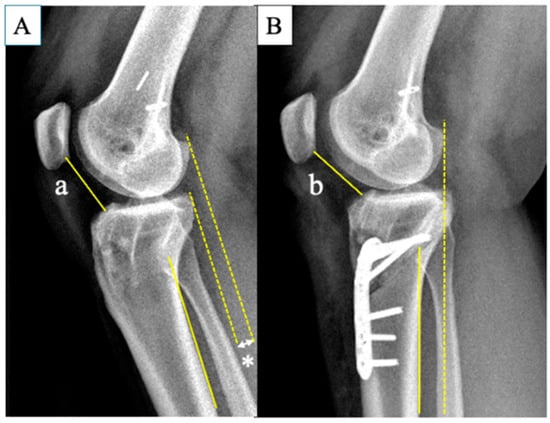

| PTS (degree) | Preoperative | 14.5 ± 1.6 |

| Postoperative | 5.7 ± 1.0 | |

| p value * | <0.001 | |